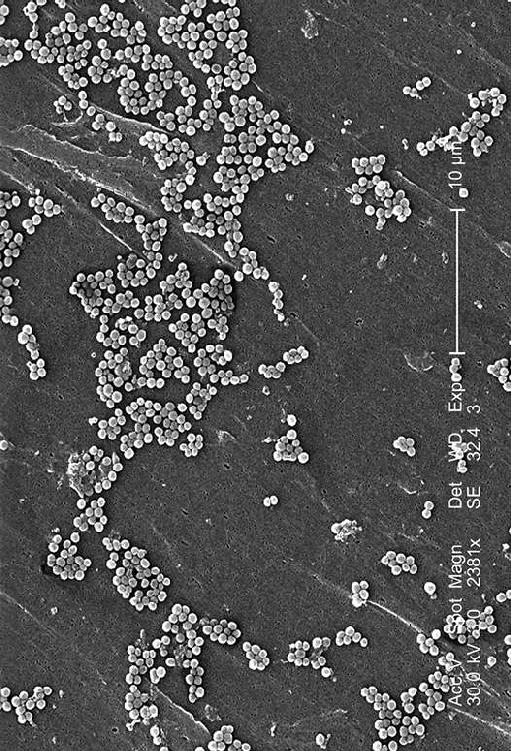

Microscopía electrónica de barrido con una preparación que muestra numerosos Staphylococcus aureus

Lo que me interesa contar en este artículo tiene más que ver con la estabilidad y tranquilidad de nuestras bacterias intestinales. La mayoría de los cientos de especies de bacterias que tenemos en el cuerpo no son malas; de hecho la mayoría son muy buenas y beneficiosas, incluso algunas colaboran en diversas tareas relacionadas con la digestión y la obtención de nutrientes para nuestro cuerpo. Pero de vez en cuando algunas bacterias de alguna de estas especies que viven con nosotros cambian de posición y pueden causar infecciones. Por ejemplo, los Staphylococcus aureus de nuestra piel pueden entrar en nuestro cuerpo por una herida, y ahí es donde puede surgir un problema. Alguna de nuestras Escherichia coli intestinales pueden llegar hasta el aparato urinario y causar una cistitis. Alguno de los Streptococcus pyogenes de nuestra boca puede llegar al sistema respiratorio y causar un dolor de garganta o una neumonía. Una bacteria normal en el sitio inadecuado puede ser un grave problema. Bueno, una sola no, quizás cientos o miles. En una infección de garganta no hay 27 bacterias, o 321, posiblemente haya miles de millones.